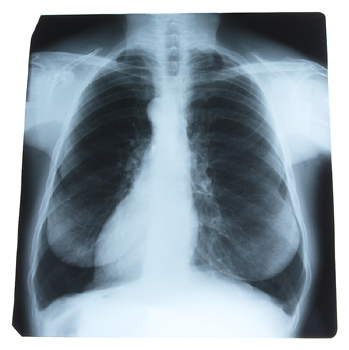

Results of the most comprehensive analysis to date of the impact of gender differences in lung cancer incidence in the United States indicate that lung cancer rates among men are on the decline, while the rate in women remains steady.Results of the most comprehensive analysis to date of the impact of gender differences in lung cancer incidence in the United States indicate that lung cancer rates among men are on the decline, while the rate in women remains steady.

A new study in the March issue of CHEST, the peer-reviewed journal of the American College of Chest Physicians, shows that, in addition to the unequal incidence of lung cancer in men and women, there are other gender-linked differences, including subtype of lung cancer and survival rate.

Researchers from the University of Michigan Medical Center and Wayne State University analyzed data of 228,572 patients (81,843 women and 146,729 men) with lung cancer who were registered in the national, population-based Surveillance, Epidemiology, and End Results (SEER) database between 1974 and 1999. Researchers found that the incidence of lung cancer in men reached a peak in 1984, when 72.5 of every 100,000 men had the disease, then declined to 47 per 100,000 men in 1991. In sharp contrast, the incidence of lung cancer in women continued to rise to a peak with 33.1 per 100,000 women in 1991, and then remained relatively stable at 30.2 to 32.3 per 100,000 women from 1992 to 1999. These variations have resulted in a male/female incidence ratio change from 3.56:1 in 1975 to 1.5:1 in 1999. For both men and women, the median age of diagnosis was 66 years. Women made up 40.9% of patients under the age of 50 but only 35.4% of patients over the age of 50.